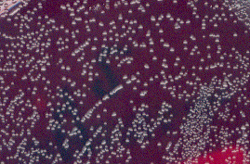

- Le réisolement à partir d'une colonie sur gélose au sang frais et celle au sang cuit donne l'aspect suivant après 48 h d'incubation à 37°C en aérobiose :